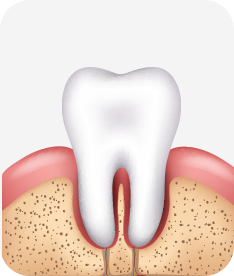

치주염 단계별 증상

건강한 상태

치아 주위의 잇몸이 핑크색을 띄며, 잇몸에서 피가 나지 않음.

스케일링을 6개월 ~ 1년 주기로 받고 올바른 칫솔질로 건강한 치주 조직을 유지